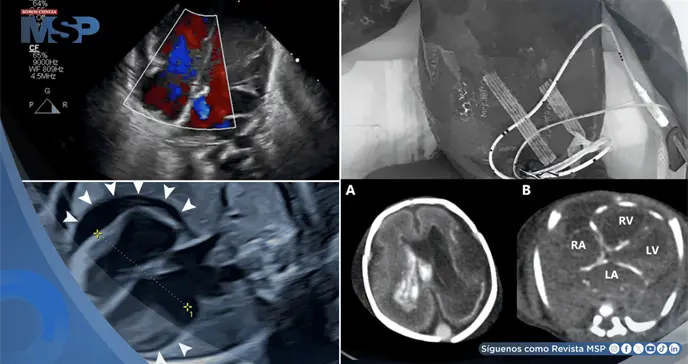

Los estudios revelaron bradicardia sinusal persistente de 100 latidos por minuto, acompañada de un derrame pericárdico circunferencial de 7-8 milímetros de ancho. Estos hallazgos se completaron con la aparición progresiva de dilatación del ventrículo derecho y múltiples lesiones hiperecoicas en el parénquima hepático, configurando un cuadro de afectación multisistémica de origen indeterminado.

Los estudios complementarios revelaron anemia severa, trombocitopenia marcada y coagulopatía grave, mientras la ecocardiografía demostró insuficiencia mitral y tricuspídea severa. Ante la sospecha fundada de infección herpética congénita por las lesiones cutáneas características, se inició tratamiento empírico con aciclovir.

La tomografía computarizada post mortem reveló hallazgos compatibles con infección congénita diseminada, incluyendo dilatación ventricular derecha, hemorragia intracraneal y calcificaciones en pared cardíaca, hígado y glándulas suprarrenales. Cabe destacar que la madre resultó asintomática pero con serología positiva para infección reciente por VHS, evidenciando la posibilidad de transmisión vertical sin sintomatología materna aparente.